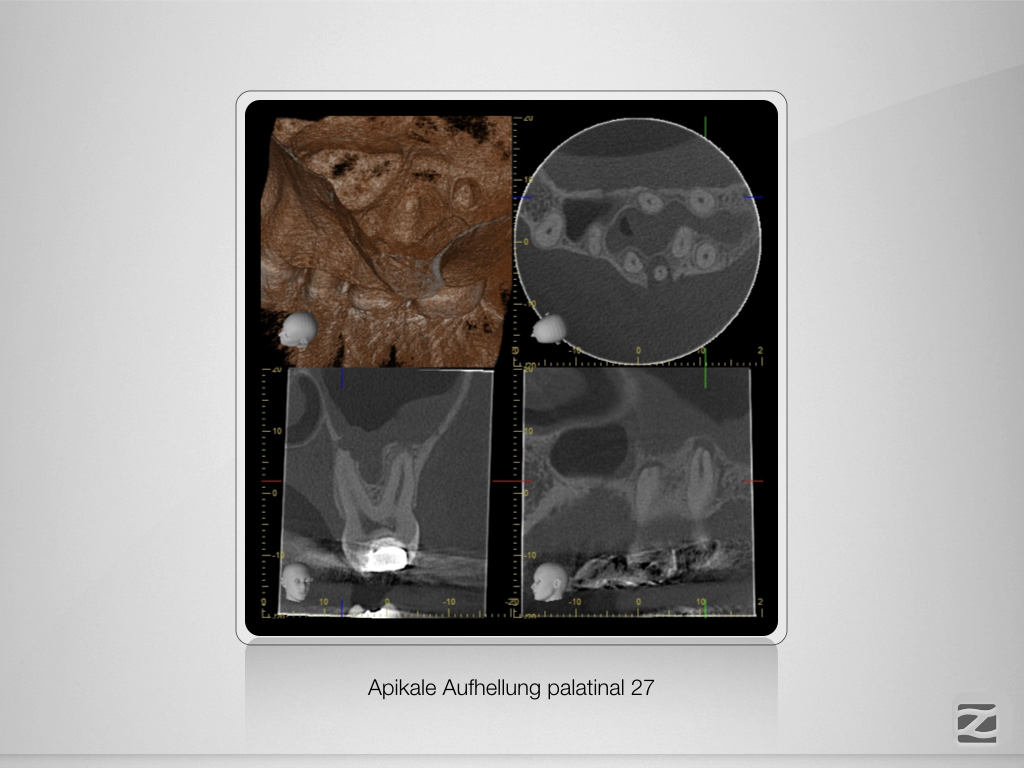

Eene, meene, muh …